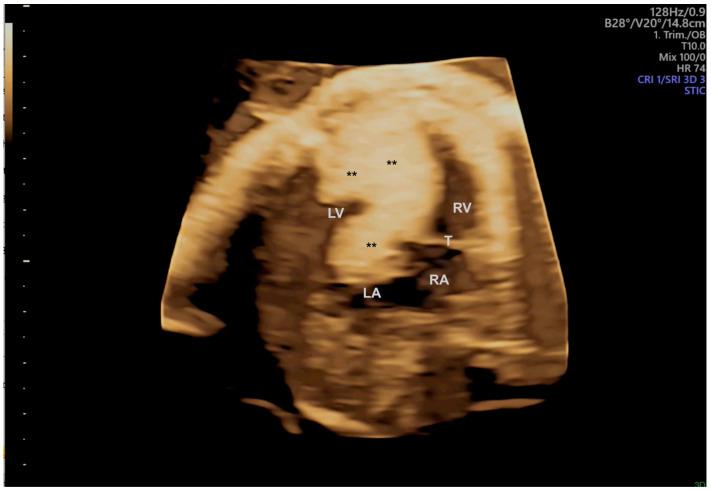

Congenital heart defects (CHDs) are the most common congenital defect, occurring in approximately 1 in 100 live births and being a leading cause of perinatal morbidity and mortality. Of note, approximately 25% of these defects are classified as critical, requiring immediate postnatal care by pediatric cardiology and neonatal cardiac surgery teams. Consequently, early and accurate diagnosis of CHD is key to proper prenatal and postnatal monitoring in a tertiary care setting. In this scenario, fetal echocardiography is considered the gold standard imaging ultrasound method for the diagnosis of CHD. However, the availability of this examination in clinical practice remains limited due to the need for a qualified specialist in pediatric cardiology. Moreover, in light of the relatively low prevalence of CHD among at-risk populations (approximately 10%), ultrasound cardiac screening for potential cardiac anomalies during routine second-trimester obstetric ultrasound scans represents a pivotal aspect of diagnosing CHD. In order to maximize the accuracy of CHD diagnoses, the views of the ventricular outflow tract and the superior mediastinum were added to the four-chamber view of the fetal heart for routine ultrasound screening according to international guidelines. In this context, four-dimensional spatio-temporal image correlation software (STIC) was developed in the early 2000s. Some of the advantages of STIC in fetal cardiac evaluation include the enrichment of anatomical details of fetal cardiac images in the absence of the pregnant woman and the ability to send volumes for analysis by an expert in fetal cardiology by an internet link. Sequentially, new technologies have been developed, such as fetal intelligent navigation echocardiography (FINE), also known as "5D heart", in which the nine fetal cardiac views recommended during a fetal echocardiogram are automatically generated from the acquisition of a cardiac volume. Furthermore, artificial intelligence (AI) has recently emerged as a promising technological innovation, offering the potential to warn of possible cardiac anomalies and thus increase the ability of non-cardiology specialists to diagnose CHD. In the early 2010s, the advent of 3D reconstruction software combined with high-definition printers enabled the virtual and 3D physical reconstruction of the fetal heart. The 3D physical models may improve parental counseling of fetal CHD, maternal-fetal interaction in cases of blind pregnant women, and interactive discussions among multidisciplinary health teams. In addition, the 3D physical and virtual models can be an useful tool for teaching cardiovascular anatomy and to optimize surgical planning, enabling simulation rooms for surgical procedures. Therefore, in this review, the authors discuss advanced image technologies that may optimize prenatal diagnoses of CHDs.

先天性心脏病(CHD)是最常见的先天性缺陷,约每100例活产中就有1例发生,是围产期发病和死亡的主要原因。值得注意的是,这些缺陷中约25%被归类为重症,需要儿科心脏病学和新生儿心脏外科团队在出生后立即进行护理。因此,在三级医疗环境中,早期准确诊断CHD是进行适当产前和产后监测的关键。在这种情况下,胎儿超声心动图被认为是诊断CHD的金标准成像超声方法。然而,由于需要合格的儿科心脏病学专家,这种检查在临床实践中的可用性仍然有限。此外,鉴于高危人群中CHD的患病率相对较低(约10%),在常规孕中期产科超声扫描期间对潜在心脏异常进行超声心脏筛查是诊断CHD的一个关键方面。为了最大限度地提高CHD诊断的准确性,根据国际指南,在胎儿心脏的四腔心视图中增加了心室流出道和上纵隔的视图用于常规超声筛查。在这种背景下,四维时空图像相关软件(STIC)于21世纪初开发。STIC在胎儿心脏评估中的一些优点包括在孕妇不在场的情况下丰富胎儿心脏图像的解剖细节,以及能够通过互联网链接将容积发送给胎儿心脏病学专家进行分析。随后,开发了新技术,如胎儿智能导航超声心动图(FINE),也称为“5D心脏”,其中在胎儿超声心动图检查期间推荐的九个胎儿心脏视图是从心脏容积采集中自动生成的。此外,人工智能(AI)最近作为一种有前途的技术创新出现,有可能警告可能的心脏异常,从而提高非心脏病学专家诊断CHD的能力。在21世纪10年代初,3D重建软件与高清打印机的出现使得胎儿心脏的虚拟和3D实体重建成为可能。3D实体模型可以改善对胎儿CHD的家长咨询、盲孕孕妇的母婴互动以及多学科医疗团队之间的互动讨论。此外,3D实体和虚拟模型可以成为教授心血管解剖学和优化手术规划的有用工具,为手术操作提供模拟室。因此,在本综述中,作者讨论了可能优化CHD产前诊断的先进图像技术。